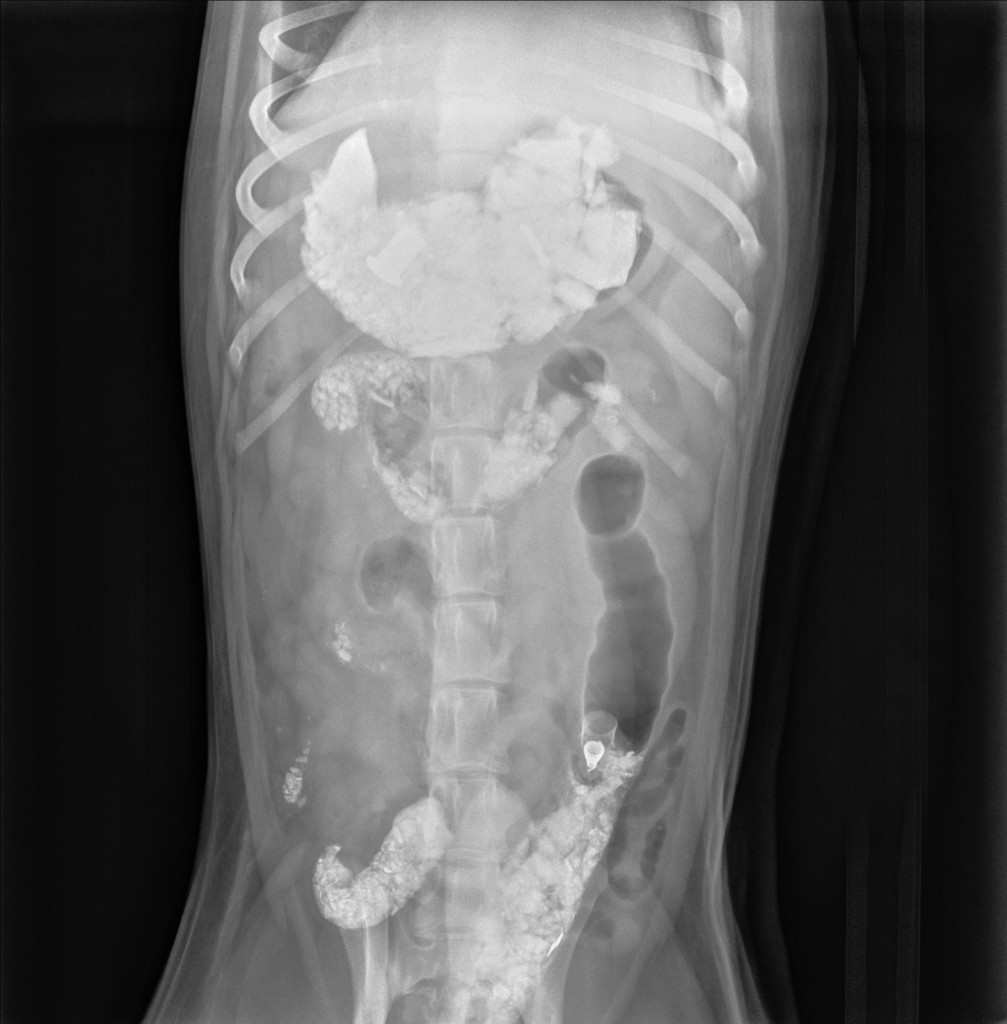

Scene #3: Problem Revealed

“Oh my, it seems you have eaten a collection of rocks!”

773BB21B-